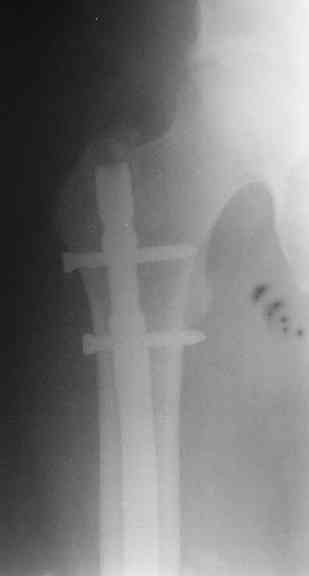

СМ> Если имеются под рукой Р-снимки, продемонстрируйте, плиз.

Вот несколько. С тисками и трубой на днях сделаем.

> Вот несколько. С тисками и трубой на днях сделаем.

Саша, последний штифт, пожалуй, перегнули?

> Саша, последний штифт, пожалуй перегнули?

Там заход сделан как для прямого штифта, не через вертел.

И правда, не через вертел. Тогда зачем гнули?